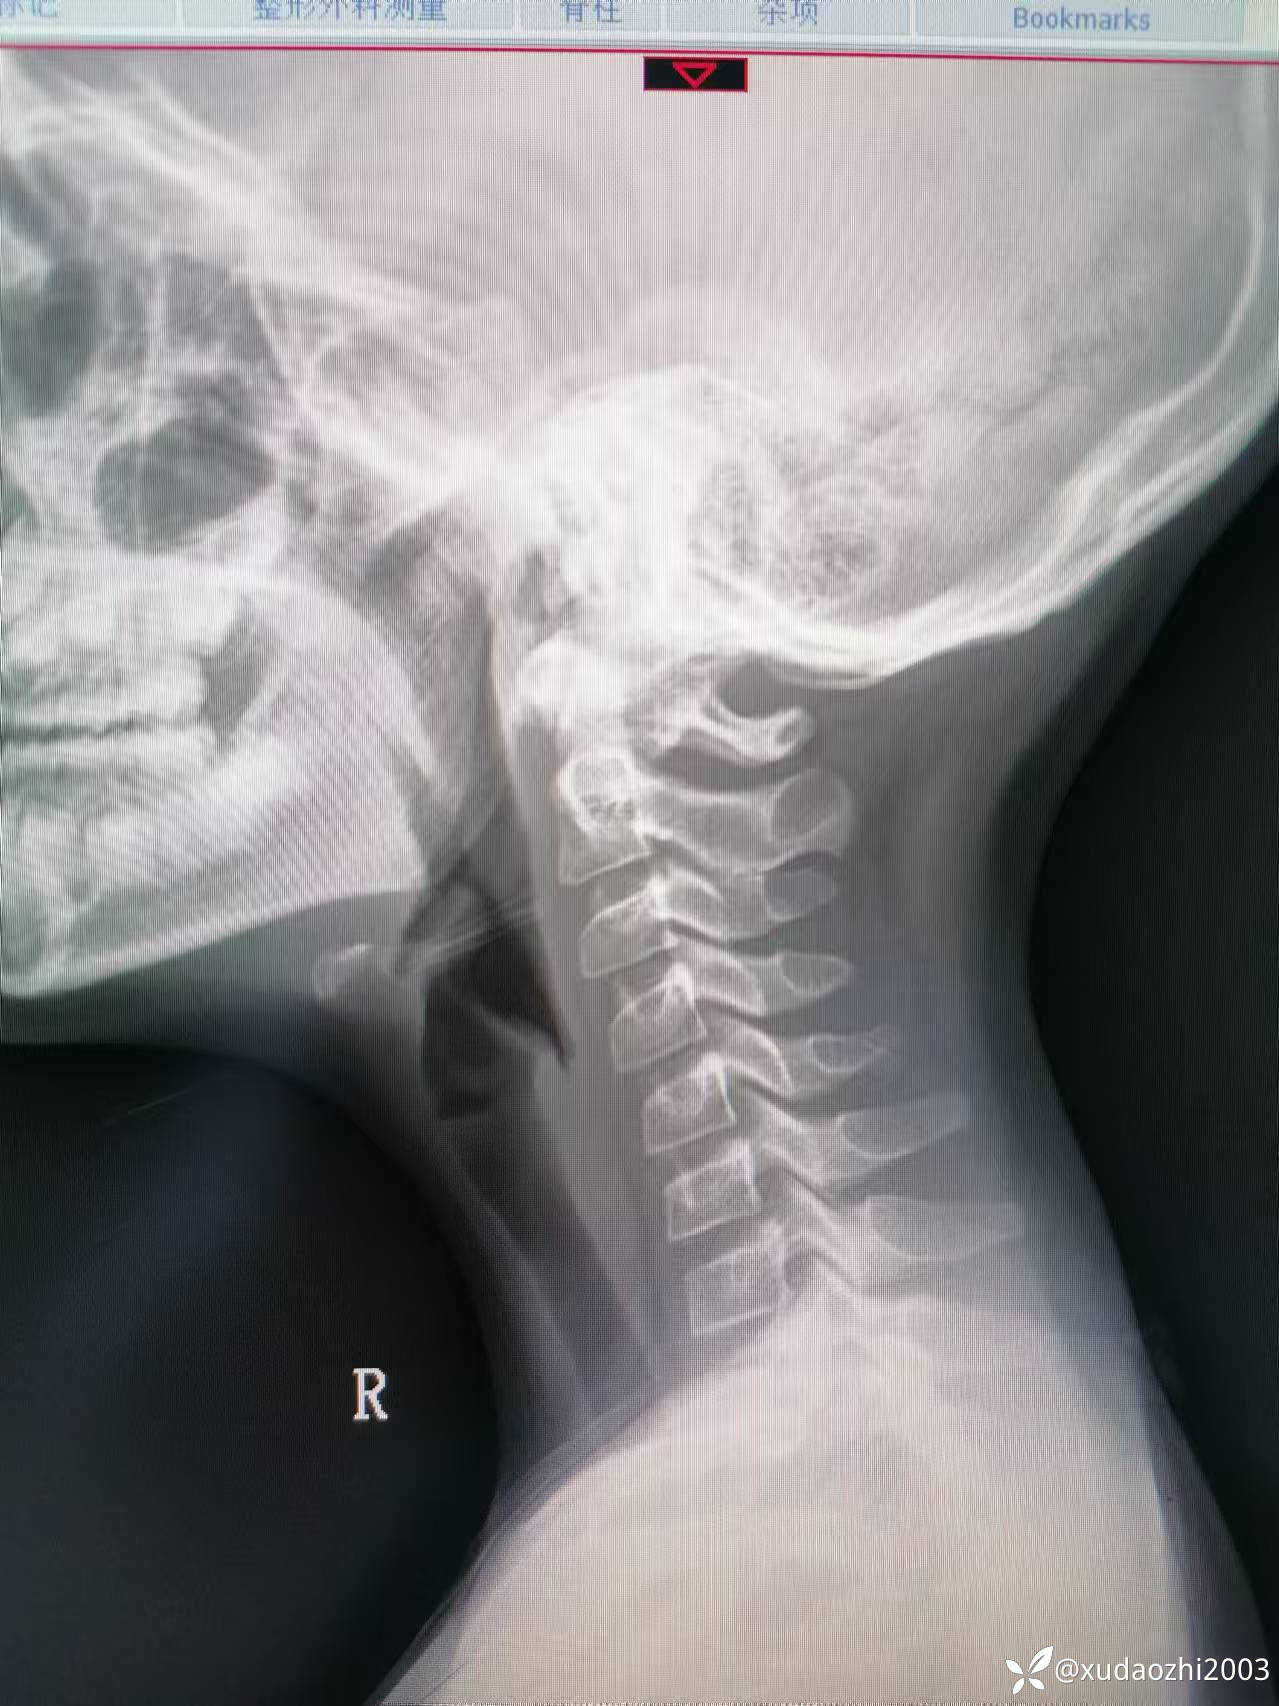

【现病史及既往史】:5月前的某一天曾进食蘑菇,几天后出现恶心呕吐,腹胀,逐渐发展至四肢无力,无法站起,于当地医院给予罗红霉素、补液等对症支持治疗,曾行血液化验检查后除了提示A型肉毒毒素阳性外,余无特殊异常,给予肉毒素针等治疗后好转。但患者嗜睡及晨起不能唤醒呈间断发作,发作时每日早晨约9点才能醒来,醒来时肢体无力,不能活动,约1小时候逐渐肌力恢复,可自主行走。曾去当地省会儿童医院,北京等医院神经科,心理科诊治(监护人诉曾行颅脑及颈髓核磁共振检查未见异常发现,两医院分别行腰穿脑脊液检查结果提示无异常,做过心理筛查未提示心理问题),未见明显改善,曾去北京某中医医院以“颈椎寰枢关节半脱位"为诊断住院治疗,经手法调理颈椎后见明显缓解,后经治疗后出院,但上述症状间断发作,多次请假治疗,但学习成绩未受到影响,学习记忆力无改变。目前每日晨晚醒,呼唤不醒,睡眠期间无抽动、无痉挛、无秽语,醒来后肌力弱、约经1小时后肌力逐渐恢复,醒来后神志清,精神一般,肌力及肌张力稍弱(考虑与废用性有关),生理反射存在,病理反射无。发病前数天患儿与一同学有头部碰撞史,无昏迷,无恶心呕吐。患儿嗜食面食与肉类,不喜水果和蔬菜。